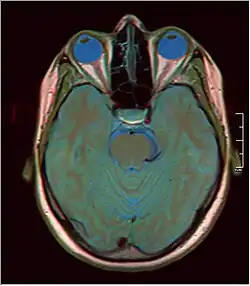

De nombreuses structures cérébrales et processus physiologiques sont impliqués dans la souffrance. Diverses hypothèses tentent de rendre compte de l'expérience de la souffrance. L'une d’elles, la théorie du chevauchement de la douleur suggère que la douleur physique et la douleur sociale, à savoir deux types radicalement différents de souffrances, partagent une base phénoménologique et neurologique commune. En effet, des observations en neuro-imagerie ont montré que le cortex cingulaire s’active quand l’individu souffre de détresse sociale ou de douleur physique[4].